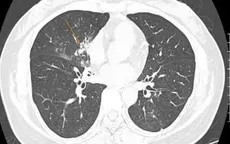

Phế cầu khuẩn: Nguyên nhân hàng đầu gây bệnh viêm phổi nhưng ít được biết đến

VTV.vn - Chi phí điều trị một ca viêm phổi có thể lên đến 710 triệu đồng, trong khi chủ động phòng ngừa bằng các biện pháp đơn giản, hiệu quả, tiết kiệm lại chưa được chú trọng.